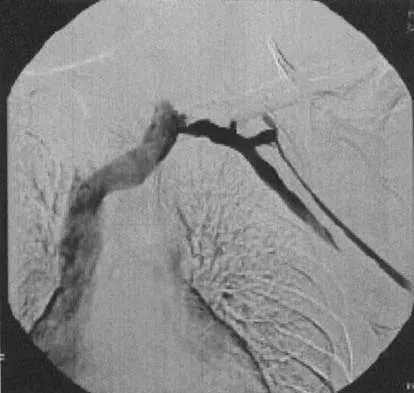

A well-developed college football player reports swelling and a heaviness in the arm after lifting weights. Examination reveals that distal pulses are normal and equal in both arms. A venogram is shown in Figure 13. What is the most likely cause of this condition?

Explanation